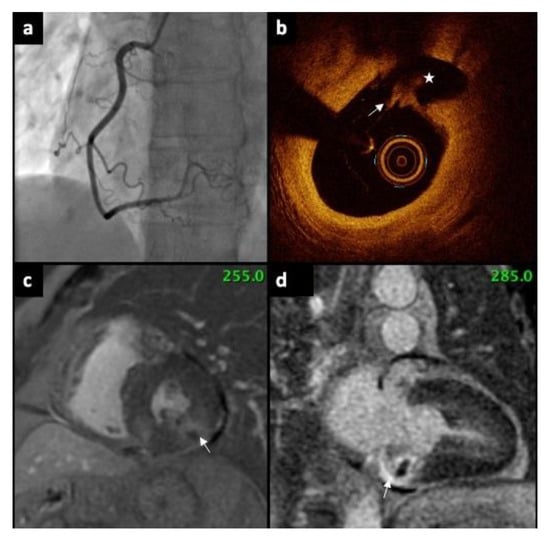

Underlying Causes of Myocardial Infarction with Nonobstructive Coronary Arteries: Optical Coherence Tomography and Cardiac Magnetic Resonance Imaging Pilot Study

| Plaque rupture, n (%) | 2 (20) |

| Plaque erosion, n (%) | 2 (20) |

| Spontaneous coronary artery dissection, n (%) | 2 (20) |

| Presence of thrombus, n (%) | 3 (30) |

| Negative OCT, n (%) | 3 (30) |

| Subendocardial, n (%) | 5 (50) |

| Transmural, n (%) | 7 (70) |

| MI, n (%) | 7 (70) |

| Myocarditis, n (%) | 2 (20) |